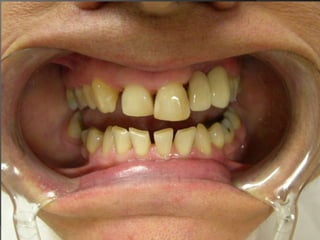

El análisis para seleccionar la ubicación de la línea de terminación se enfoca en 2 componentes:Estética vs HigieneExtensión mínima dentro del surco gingivalDisimular la zona de asentamientoFacilitar la higiene del pacienteNecesidad de aumentar la retención y estabilidadLínea de Sonrisa

PRINCIPIOS ESTÉTICOSRestauraciones con forma, contorno y color adecuados